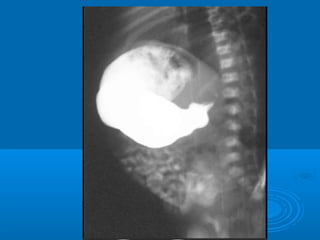

2-Barium meal: for cases with difficulty in diagnosis2-Barium meal: for cases with difficulty in diagnosis ::

①①distention of the stomachdistention of the stomach

②②strong gastric wavesstrong gastric waves

③③elongated and narrow pyloric channel “String Sign”elongated and narrow pyloric channel “String Sign”

④④delayed gastric emptyingdelayed gastric emptying

Barium meal